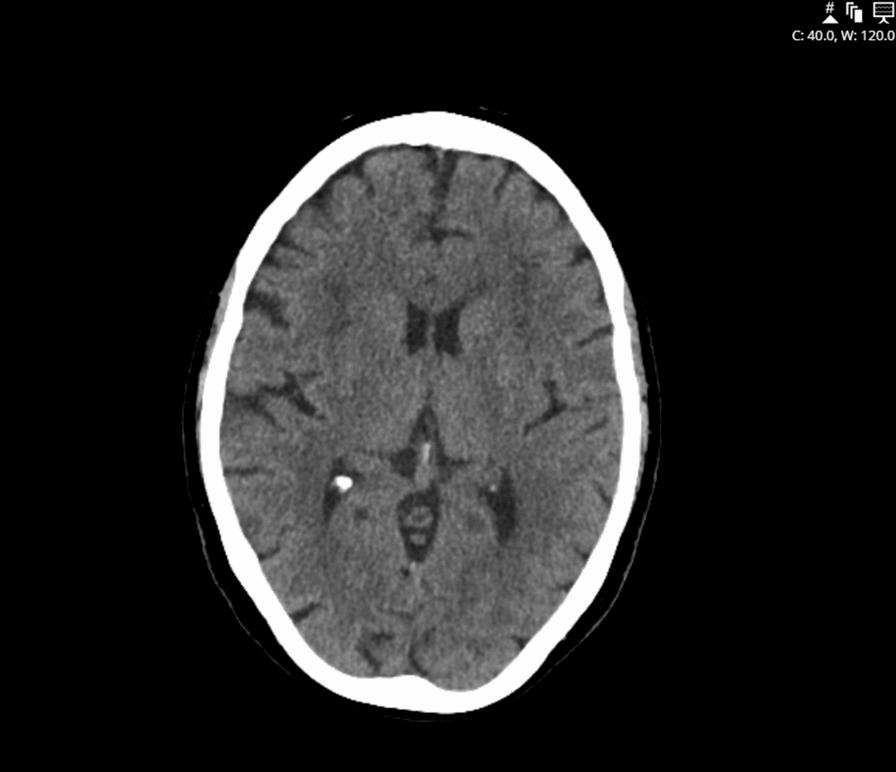

We present a compelling case of a 73-year-old Caucasian female presenting with abrupt onset of isolated dysarthria. Despite initial treatment for a presumed lacunar stroke, subsequent evaluations led to her diagnosis of a myasthenic crisis. Within 72 h of admission, the patient developed dysphagia and shortness of breath, requiring supplemental oxygen. The case highlights the sequential progression of events from the atypical presentation of isolated dysarthria and its course to the management of a myasthenic crisis.

Our reported case focuses on the discussion of myasthenia that mimicked a lacunar stroke and was finally diagnosed at a critical time of medical crisis. This case highlights the imperative notion that isolated dysarthria in elderly individuals warrants vigilant monitoring for possible myasthenia gravis, given the low incidence of lacunar stroke presenting with only dysarthria.

我们呈现了一个引人注目的病例,一名 73 岁的白人女性突发孤立性构音障碍。尽管最初被诊断为疑似腔隙性卒中进行了治疗,但随后的评估导致她被诊断为肌无力危象。入院后 72 小时内,患者出现吞咽困难和呼吸急促,需要补充氧气。该病例强调了从孤立性构音障碍的非典型表现及其进展到肌无力危象的管理的一系列事件的顺序。

我们报告的病例重点讨论了肌无力的表现类似于腔隙性卒中,最终在医疗危机的关键时刻得到了诊断。该病例突出表明,老年人孤立性构音障碍需要警惕可能的重症肌无力,因为腔隙性卒中仅表现为构音障碍的发生率较低。